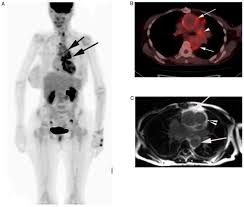

Best FDG PET CT Scan in Green Park